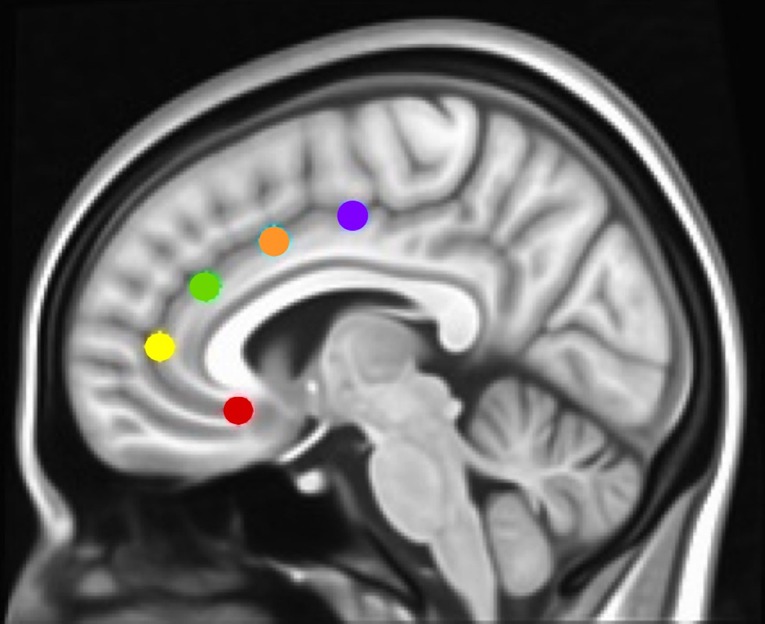

To determine how networks associated with specific executive control domains changed across time between groups, we examined rsFC of five functionally distinct anterior cingulate cortex (ACC, f1) networks for which changes across time have been examined in healthy controls as well as in adolescents with CUD (ref. 17, ref. 19): caudal ACC [MNI (Montreal Neurological Institute) coordinates: x = ±5, y = 10, z = 47), dorsal ACC (x = ±5, y = 14, z = 42), rostral ACC (x = ±5, y = 34, z = 28), perigenual ACC (x = ±5, y = 47, z = 11), and subgenual ACC (x = ±5, y = 25, z = 10). Each of these ACC regions has been associated with specific executive control domains: motor control, cognitive/attentional control, conflict monitoring, internalization/mentalizing, and emotional regulation, respectively (ref. 17, ref. 42). As a secondary analysis and to determine how reward processing networks might vary between groups, we examined rsFC of the nucleus accumbens [NAcc; MNI coordinates: x = 12, y = 10, z = −8 (right) and x = −10, y = 10, z = −8 (left)] (ref. 43), using 3.5 mm spherical seeds placed bilaterally [as in Ref. (ref. 27)]. Because we did not hypothesize laterality effects within ACC or NAcc networks (ref. 42, ref. 44), and to minimize the number of regions of interest examined, we converged left and right seeds, resulting in five bilateral ACC seeds (ref. 17, ref. 19) and one bilateral NAcc seed (ref. 27). Each bilateral spherical seed covered 257 voxels in 1 × 1 × 1 mm MNI space. For each participant’s preprocessed and denoised residual data, mean time series were extracted for each of the six bilateral seed regions.